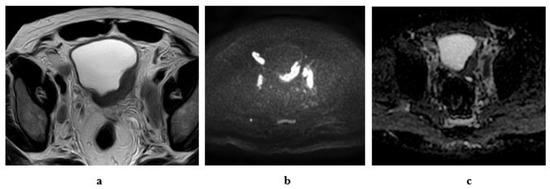

2.6.2. Diffusion-Weighted Imaging (DWI)

2.6.3. Dynamic Contrast-Enhanced (DCE) Imaging

- Stage T1: Intact muscle layer adjacent to the tumor and displays hypointense SI at high resolution T2W sequence without early enhancement on dynamic study.

- Stage T2: Interrupted hypointense line of the muscle layer with early enhancement of the tumor with no extravesical fat invasion.

- Stage T3: irregular outer boundary of the tumor with distortion of the extravesical fat with the same SI of the tumor.

- Stage T4: Tumor infiltrates the surrounding organs or pelvic walls.